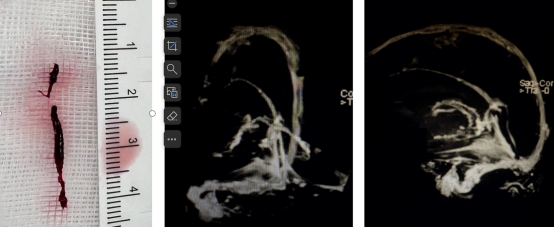

术中血栓及术后复查CE-MRV

术中取出血栓复查MRV正位复查MRV侧位

患者转入神经内科后,行腰穿及核磁共振检查,考虑患者颅内静脉窦广泛血栓形成,病情危重。患者有行颅内静脉窦造影及取栓指征,与患者家属商议后,第一时间脑血管造影,明确颅内静脉窦血栓,并给与颅内静脉窦取栓,5小时后患者静脉窦再通,成功回病房进一步抗凝药物治疗。